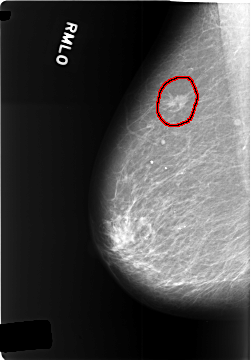

C_0340_1.RIGHT_MLO

FILE: C_0340_1.RIGHT_MLO.OVERLAY

TOTAL_ABNORMALITIES 1

ABNORMALITY 1

LESION_TYPE MASS SHAPE OVAL MARGINS SPICULATED

ASSESSMENT 5

SUBTLETY 5

PATHOLOGY MALIGNANT

TOTAL_OUTLINES 1

BOUNDARY